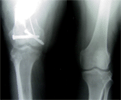

Malunion femur with Knee osteoarthritis in a 54 years old female Chinese

Pre

Op